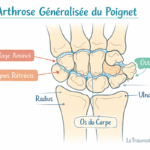

Arthrose du poignet

L’arthrose résulte de l’usure du cartilage. Elle est souvent secondaire à un traumatisme ancien ou à une maladie inflammatoire. Elle provoque :

- douleur mécanique,

- raideur articulaire,

- craquements.